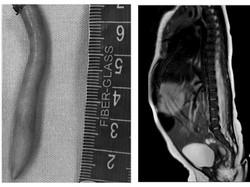

Sejumlah rusa di Taman Balekambang dipindahkan ke Taman Sriwedari Solo. Kondisi rusa kini disebut tak terurus, kotor dan kurus. Begini kondisinya.